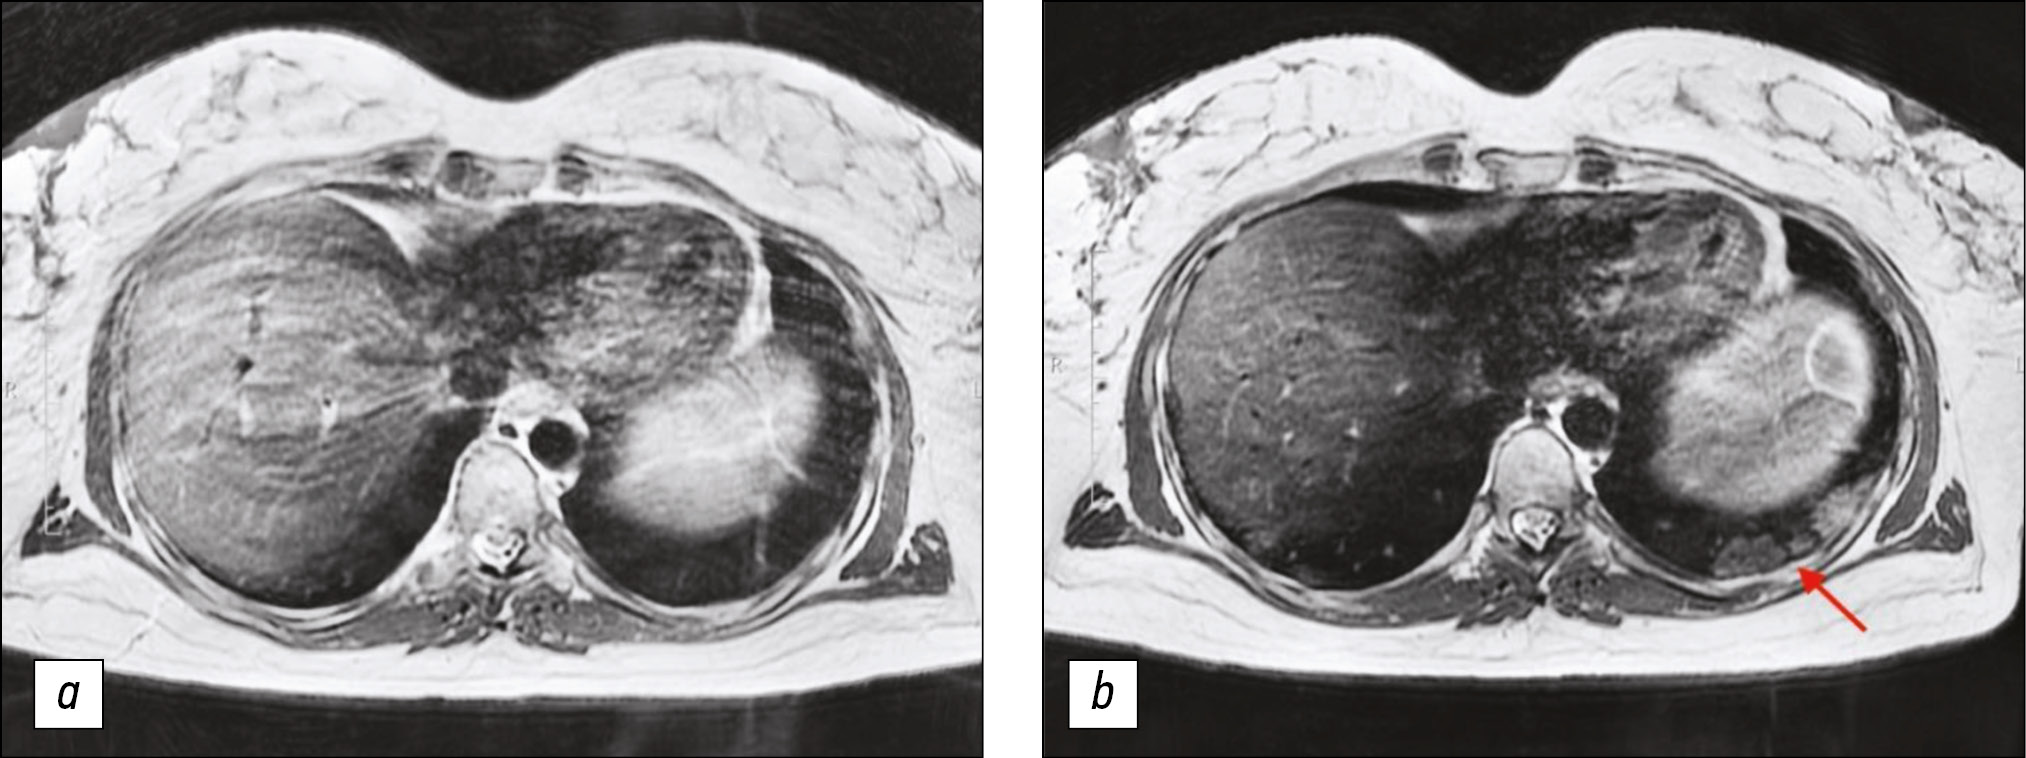

Lung MRI was performed 7 days later, because the condition did not improve during treatment, and dry, ineffective cough worsened. MRI performed that time revealed zones of infiltration (Figs. 1, 2) in the lower lobes of the lungs.

Figure 1. Chest magnetic resonance imaging, T2-weighted imaging single-shot fast spin echo: a) Primary examination, b) magnetic resonance imaging 7 days later. In Fig. 1b, consolidation zones in lower lungs appeared as areas of hyperintense and isointense signals.